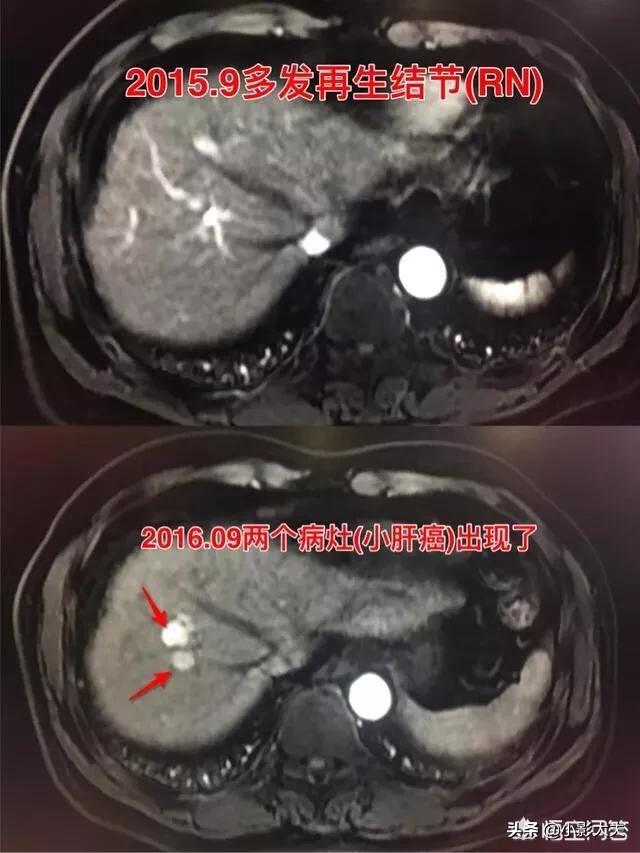

不一定!肝癌的演变要经历四个过程(下图),首先是再生结节(RN)、高级别不典型增生结节(DN癌前病变)、结节中结节、最后到小肝癌(HCC),小肝癌就是肝癌的正式形成时期(早期),慢慢长大,最后出现肝内或者全身多发转移(晚期)。

肝硬化会导致很多再生结节(RN),高级别再生结节(DR),到最后肝癌形成。有些早期肝癌的患者,做了肿瘤切除或者射频消融后,过一年其他地方又新长出了癌症,有些人不能理解为什么会这样呢?因为肝硬化会导致无数个再生结节的形成,切掉一个,其他也还会转化为肝癌。但是并不是所有都会转为肝癌,不然满肝脏都是肝癌了。有人朋友会说了,那还治什么治,目前的医学治疗手段只能见一个杀一个。

这是一位43岁男性,乙肝多年,2015年9月发现肝硬化,一年时间2016年9月,两个小肝癌形成了。

所以,有肝硬化结节的一定要检查随诊复查,半年到一年一次超声、CT或者磁共振检查。尽早发现早期肝癌,尽早处理。